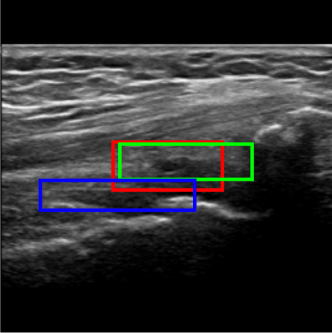

Considering the detection problem, Figure 10 shows US images where the two approaches detected the SQR with the lowest and the highest IoU. In Figure 10a, the Multi-task approach wrongly detects as SQR an image region that is similar to an actual SQR in terms of position and shape, resulting in a very low value of IoU (0.330.330.33). In this case, also the Detection approach can not reliably detect the right target precisely, and indeed it detects only a small portion of the actual SQR (IoU=0.330.330.33). Instead, in the example shown in Figure 10b the Multi-task approach accurately detects the SQR (IoU=0.950.950.95), while the Detection approach identifies the same area with a lower IoU (0.68)0.68).

Figure 10c shows the US image for which the Detection approach provided the lowest IoU value. The problem is similar to that of Figure 10a: a region is erroneously recognized as a SQR because it is similar to a SQR. In this case the detected bounding box does not overlap with the ground truth, hence the IoU is zero. Instead, the Multi-Task approach basically detects the right target (IOU=0.580.580.58).

Figure 10: Detection examples. Green represents the ground truth, red and blue the results of the Multi-Task approach and Detection approach, respectively.

Figure 10d shows instead the US image for which the Detection approach provided the highest IoU value (0.960.960.96). In this case the Multi-task approach identifies the right target less precisely, resulting in a IoU of 0.550.550.55.